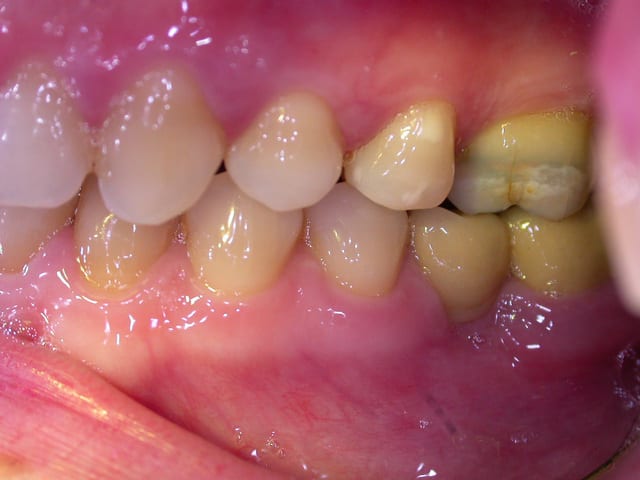

examen buccal .........voir les photos ........après ........ca vient

examen radio .........après ca vient.......

Bon controle de plaque, pas de tartre ni de colorations, inflammation en palatin seulement...